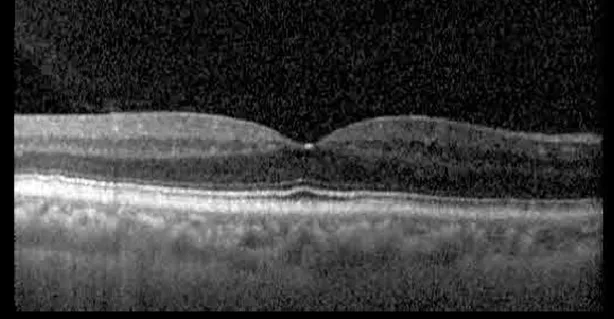

The patient began treatment with oral pemigatinib daily and was followed up for an ophthalmic examination during the second treatment cycle approximately 5 weeks into the treatment process. The patient had at this stage received 28 doses of 13.5 mg per day, which was administered in cycles of 14 on-days and 7 off-days, and had no visual or ophthalmic complaints. The non-corrected VA was OD 20/30 + 1 and OS 20/20. The OCT examinations revealed subfoveal SRF bilaterally. The fundus examination was otherwise unremarkable outside the patient’s prior documented peripheral drusen. Repeat autofluorescence was overall unchanged, though a slight hypofluorescent ring may be visualized in Figure 2. The current pemigatinib protocol recommendation for asymptomatic patients suggests no dose modification; however, with worsening presentation or positive symptoms, it is recommended to withhold pemigatinib. After discussion with the patient’s oncologist, it was decided to continue the medication at this time. Serial monitoring of the patient’s symptoms, vision, and SRF were conducted on specific days during active treatment cycles and days off-cycle to monitor the SRF. Subsequent evaluations demonstrated complete resolution of SRF while off-cycle, and asymptomatic re-accumulation of fluid while on-cycle with varying levels of VA. (Table 1) As we see demonstrated in the table below, in the later stages of the active cycles, such as day 13 of 14 of cycle 2, day 13 of 14 of cycle 3, day 13 of 14 of cycle 4, and day 14 of 14 on cycle 5, the patient’s VA showed no correlative changes based on the presence of SRF. The fluctuations in the patient’s VA certainly occurred, but were likely to be secondary to surface changes, as certain off-cycle days actually presented with lower acuities than days when the SRF was present on OCT examination.

Figure 2

| Cycle, day, on/off | VA OD; OS | CMT OD; OS | OCT OD | OCT OS |

| Prior to initiation | 20/40; 20/20−2 | 274; 275 | ![]() | ![]() |

| Cycle 2, day 13/14, on | 20/30+1; 20/20 | 365; 355 | ![]() | ![]() |

Highlights the visual acuity, central macular thickness, and the physical OCT of the macula for this patient in both the right and left eyes during various stages of the patient's chemotherapy treatment cycle.